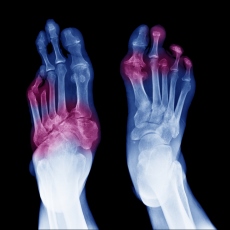

Skin symptoms may include a blue or black color, pain, numbness, and sores that produce a foul-smelling discharge. If the gangrene is internal, you may run a fever and feel unwell, and the area may be swollen and painful.